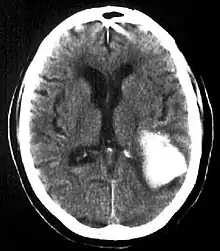

Intraparenchymal hemorrhage

Intraparenchymal hemorrhage (IPH) is one form of intracerebral bleeding in which there is bleeding within brain parenchyma. The other form is intraventricular hemorrhage (IVH).[1]

Intraparenchymal hemorrhage accounts for approximately 8-13% of all strokes and results from a wide spectrum of disorders. It is more likely to result in death or major disability than ischemic stroke or subarachnoid hemorrhage, and therefore constitutes an immediate medical emergency. Intracerebral hemorrhages and accompanying edema may disrupt or compress adjacent brain tissue, leading to neurological dysfunction. Substantial displacement of brain parenchyma may cause elevation of intracranial pressure (ICP) and potentially fatal herniation syndromes.